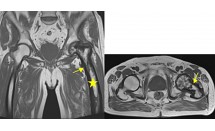

Conflit intertrochantéro-ischiatique